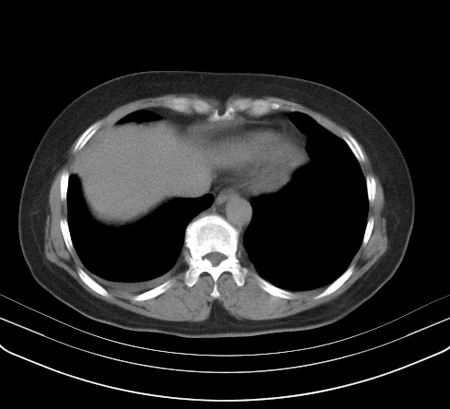

以下是引用余辉在2009-2-19 20:10:00的发言:[br]多考虑急性感染性病变,右中叶尚可见多枚小斑片状影,多为化脓性肺炎,双侧胸腔积液

以下是引用随光逐影在2009-2-19 20:33:00的发言:[br]1)考虑右肺炎症;建议抗炎治疗后复查。2)双侧胸腔积液(以右侧为甚)。

以下是引用花凤凰在2009-2-19 20:46:00的发言:[br]病人有发热,胸痛急性起病,主要病变位于右肺中叶外侧段,呈楔行改变,位于外带胸膜下,考虑为肺梗塞可能!!!!!!!!!!!!!!!!!!!!!!!!!!!!!!!!!!!